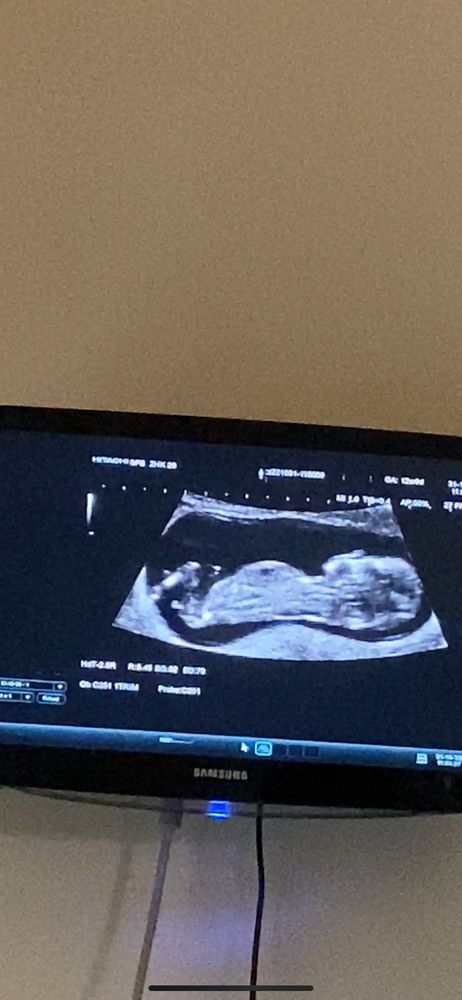

Половой бугорок

девочка

Похоже что девочка

Девочка 👧

Я бы сказала, что мальчик

Настёна , предположили девочку. Сказала больше на нее похоже

Это же уже точно девочка?) Пол малыша на 13й недельке)